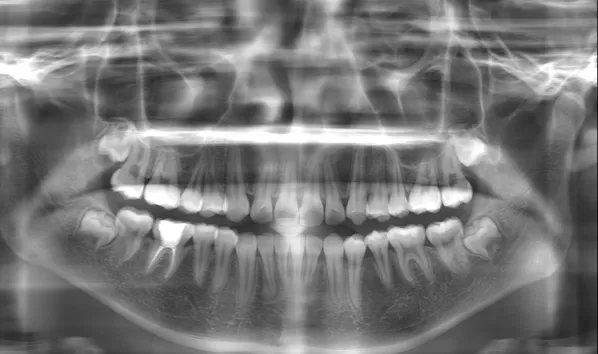

Rayons X avant le traitement

[Radiographie panoramique/Céphalogramme latéral]